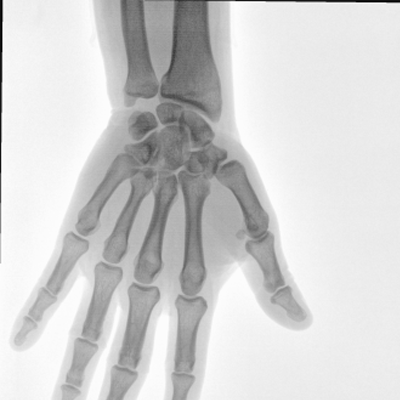

大尺寸动态平板探测器,高DQE、低噪声、图像清晰。采用多分辨率图像增强处理技术,不同部位不同图像处理算法,满足客户多样化的需求。